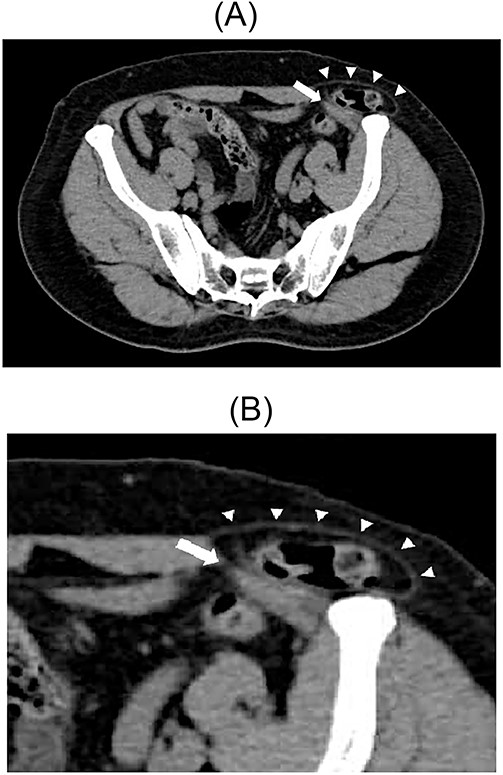

A 79-year-old male patient with a medical history of right inguinal hernia presented to the emergency department with right inguinal swelling and pain. We found the inguinal swelling, which extended toward the head, to be atypical. In addition, contrast-enhanced computed tomography (CT) scan revealed that a portion of the small intestine was incarcerated between the internal and external oblique muscles, and the hernia contents had prolapsed cranially from the hernial orifice. Furthermore, the sagittal view revealed that the contents of the hernia had prolapsed ventrally and not along the spermatic cord (Figs 1 and 2). Therefore, we diagnosed it as a right interparietal inguinal hernia, and laparoscopic hernia repair was planned. Owing to the fact that the manipulative reduction was difficult, we planned to release the incarceration first.

Contrast-enhanced CT scan; an incarcerated bowel was observed in the right inguinal region; the small bowel was incarcerated between internal and external oblique muscles; the white arrow indicates the internal oblique muscle, and the white triangles indicate the external oblique muscle.